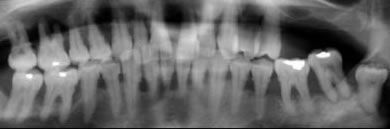

Eine initiale Diagnostik kann eine Fotodokumentation, die Erstellung diverser Indizes (z. B. Plaqueindex, API/ SBI) und Röntgenaufnahmen beinhalten. Bei den Röntgenaufnahmen wird eine Panoramaaufnahme (OPG) angefertigt. Von nicht vital reagierenden und wurzelgefüllten sowie nicht im OPG ausreichend erkennbaren Zähnen werden Zahnfilme erstellt.

Die Röntgendiagnostik gibt Auskunft über Zustand, Form und Beschaffenheit von Zahnhartsubstanz, Alveolenknochen, Desmodontalspalt und Restaurationen.